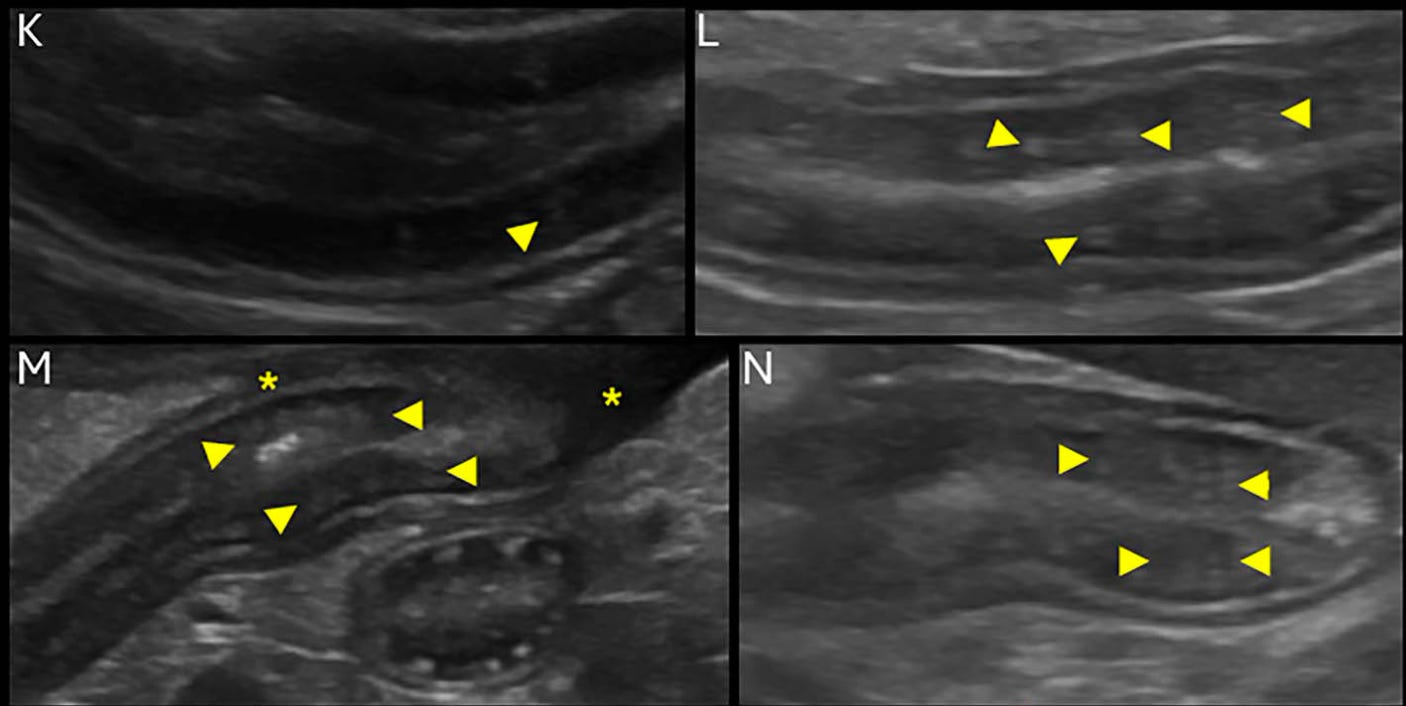

Diferentes grados de engrosamiento de la pared intestinal y la mucosa:

Diferentes grados de punteados hiperecogénicos de la mucosa: